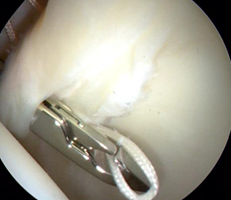

在持续牵引下首先进入髋关节中央间室,在70度镜下进行关节探查,清理增生的炎性滑膜、取出游离体、处理软骨损伤及切除病变的髋臼盂唇;对于FIA患者,磨削骨性髋臼缘去除pincer撞击,如果不存在Pincer撞击,则仅需磨削髋臼缘去皮质化,新鲜化髋臼缘形成一个弧形的、光滑的渗血骨床。对损伤的盂唇尽量予以缝合(采用可吸收锚定)。然后在非牵引下进入外周间室,30度镜下对股骨头颈处的Cam撞击进行股骨头颈成型,避免修复的盂唇组织发生撞击。(左图:关节镜下缝合盂唇;右图:缝合后的盂唇)